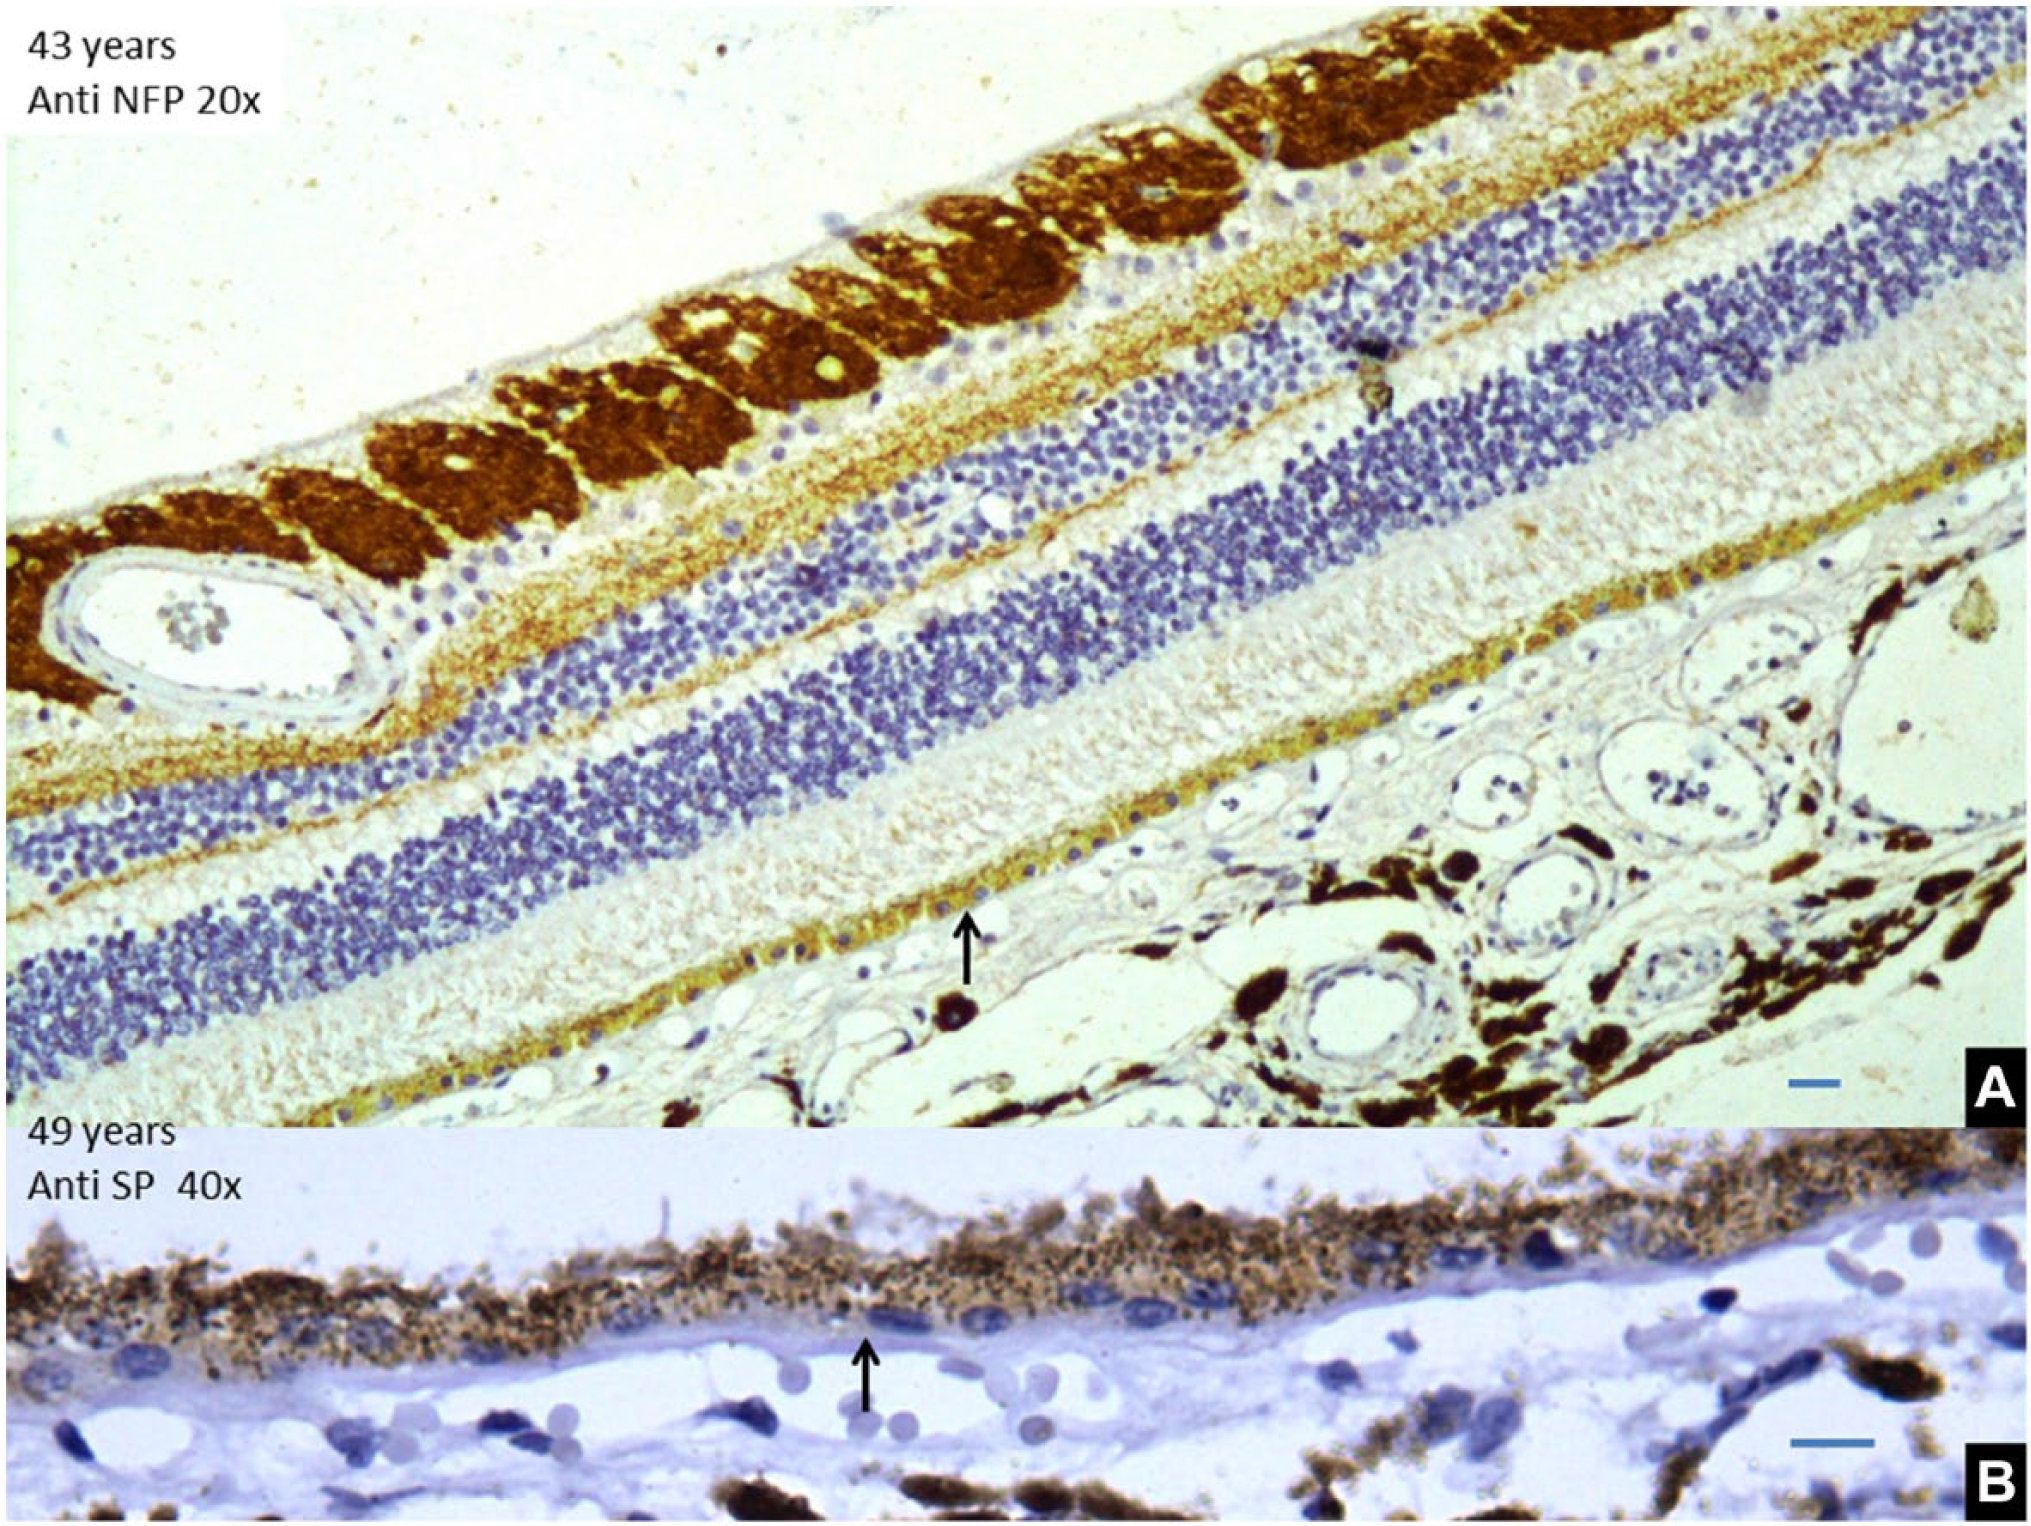

(A) Specimen of a 43-year-old retina showing RPE cells are low cuboidal cells with exposed nucleus and a decreased pigment content. Scale bar, 10 µm. (B) Thickening of Bruch’s membrane in a 49-year-old retina. Scale bar, 5 µm. Abbreviations: RPE, retinal pigment epithelium; NFP, neurofilamentary protein.

The RPE cells rest on the basement membrane that fuses with the basement membrane of the choroidal capillaries to form BM (Fig. 6). In the second decade, it was seen as a thin but distinct membrane. The ratio of BMs membrane to the diameter of the abutting choroidal capillary (b:c) was 1:6 or less. These changes are better appreciated in the slides labeled with anti-SP or anti-NFP antibodies (Figs. 1 and 2).